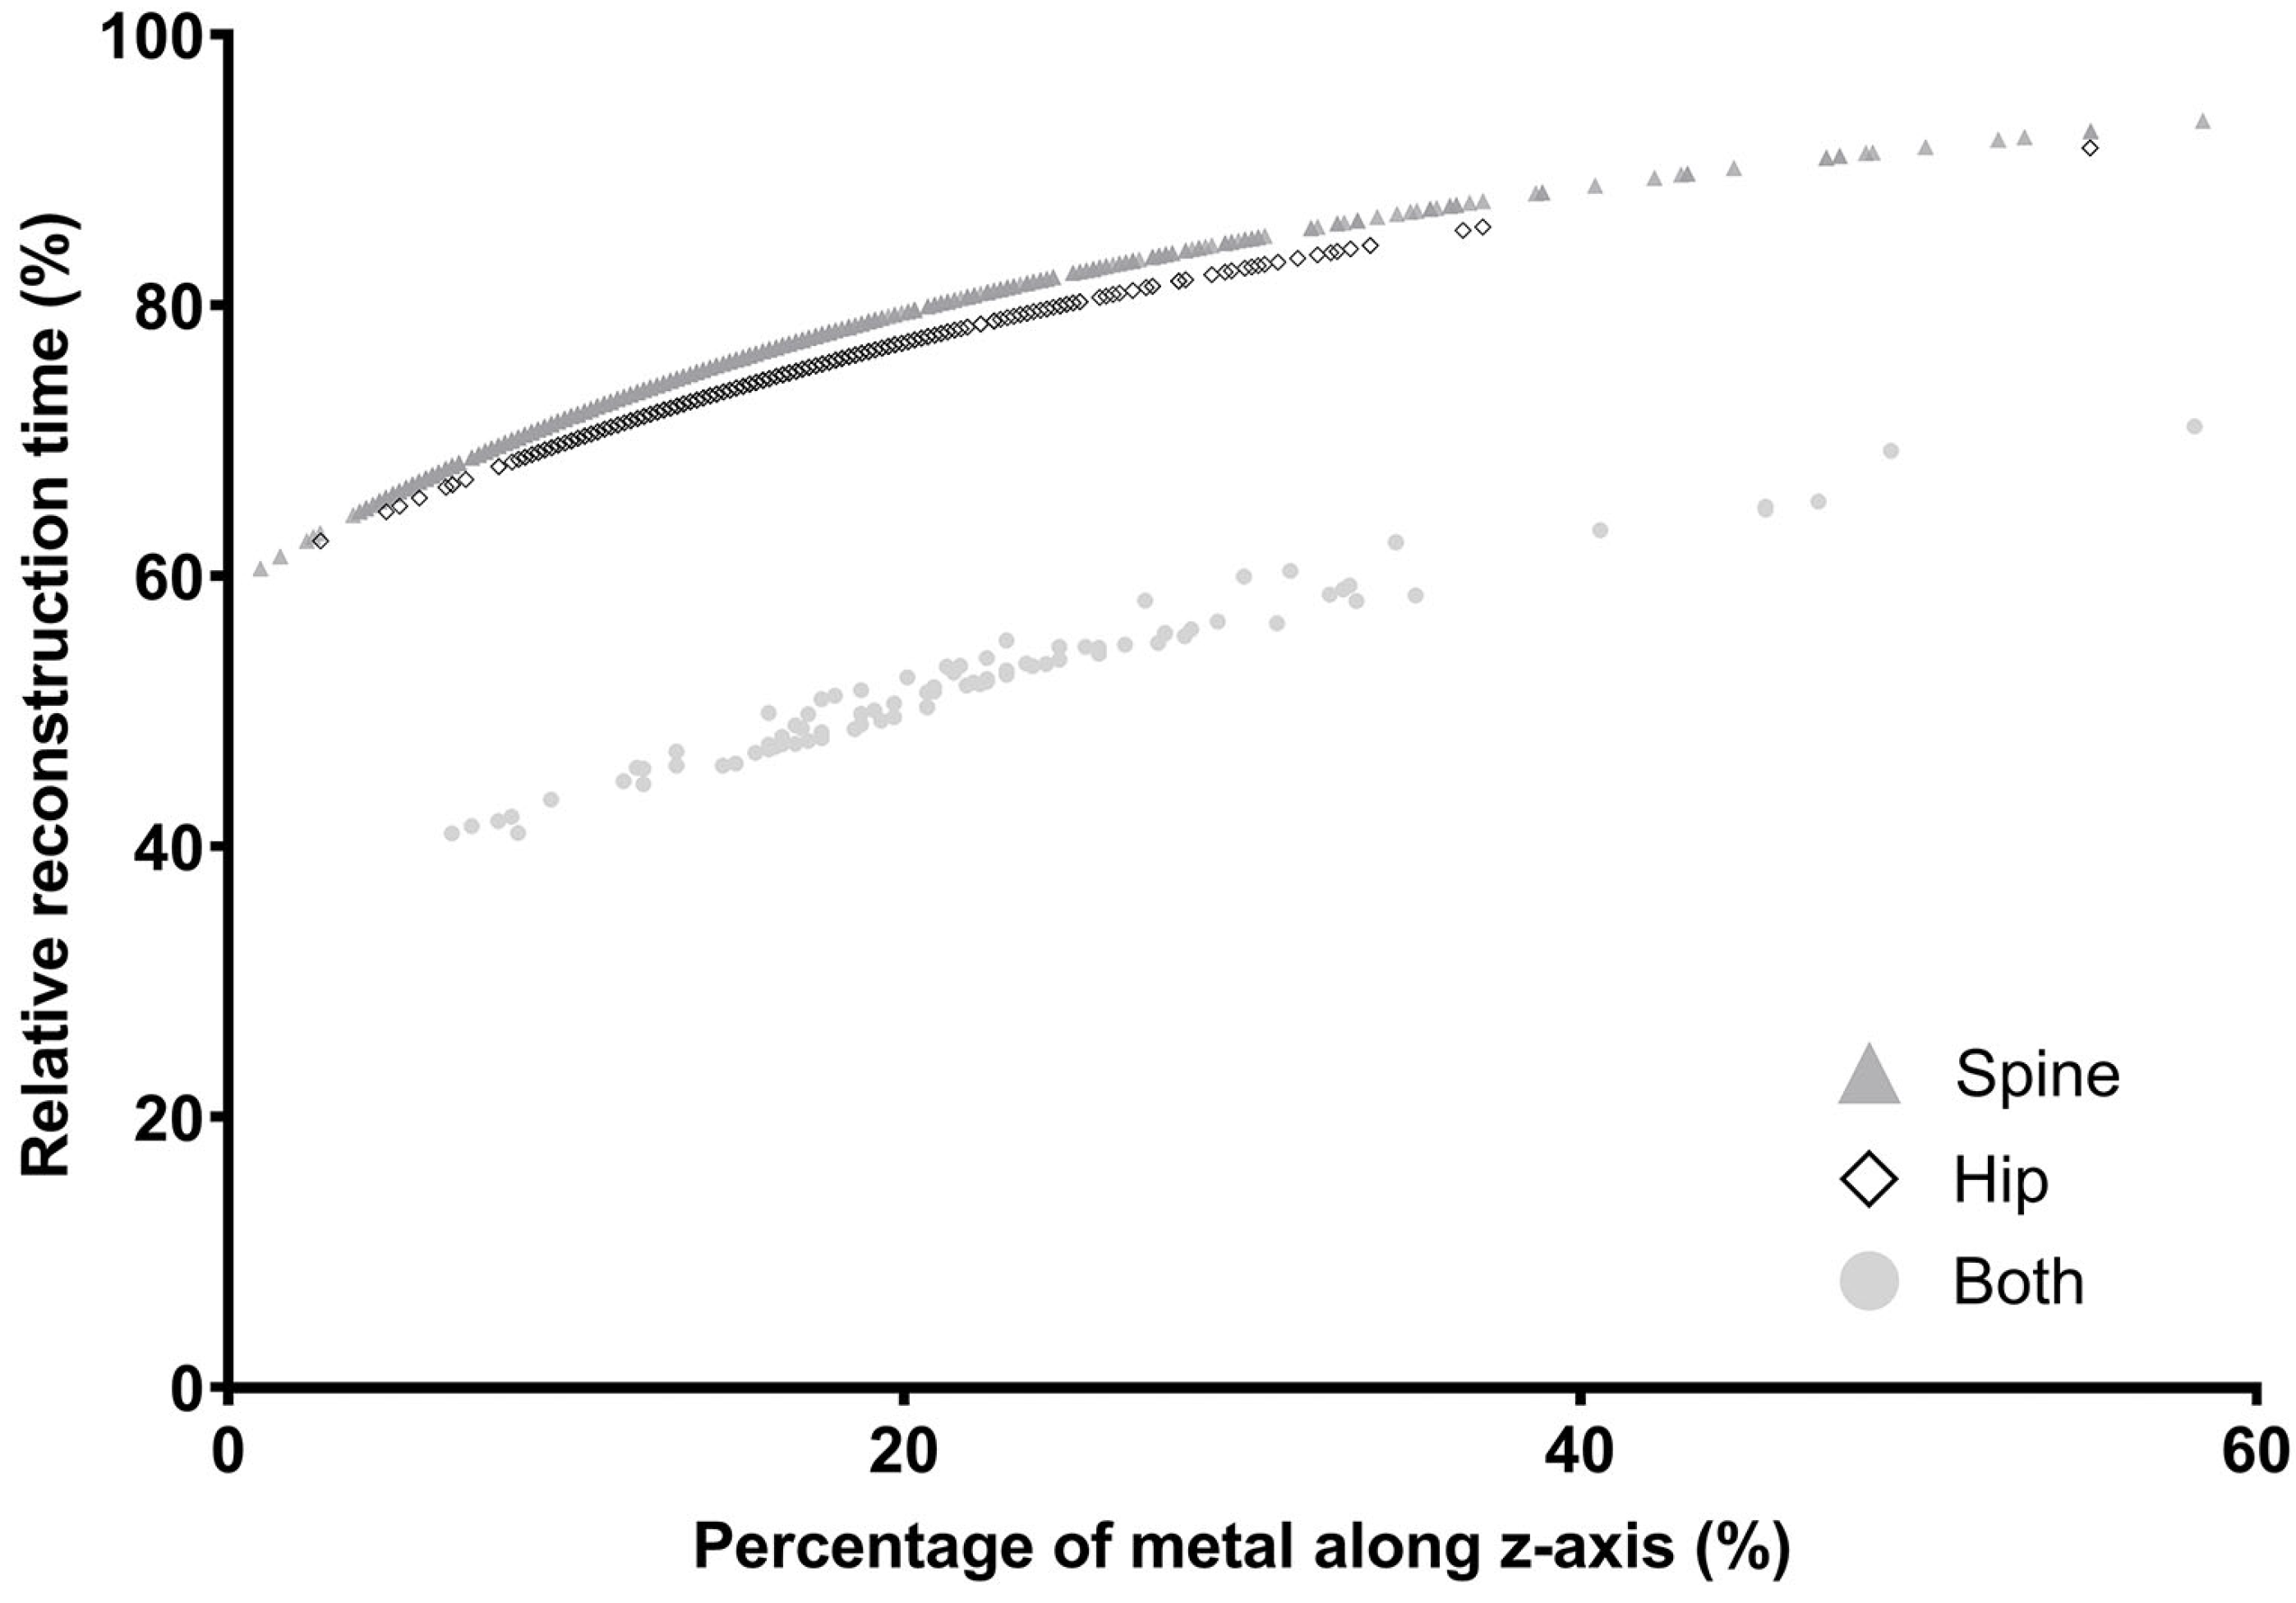

3.3. Impact on Reconstruction Time by Integrating the DLA